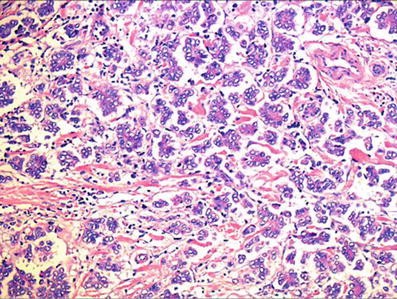

El colangiocarcinoma, aunque raro, es la segunda neoplasia maligna hepática primaria más frecuente (10 a 20% de los tumores hepáticos primarios). La edad media en el momento del diagnóstico es de 50 años.

Los tumores que involucran los conductos biliares dentro del parénquima hepático proximal a los conductos biliares de segundo orden se consideran colangiocarcinoma intrahepático y representan del 6 al 8% de los colangiocarcinomas.

Según el tipo de crecimiento, el colangiocarcinoma intrahepático se divide en tres subtipos:

- formador de masa

- infiltrante periductal

- crecimiento intraductal